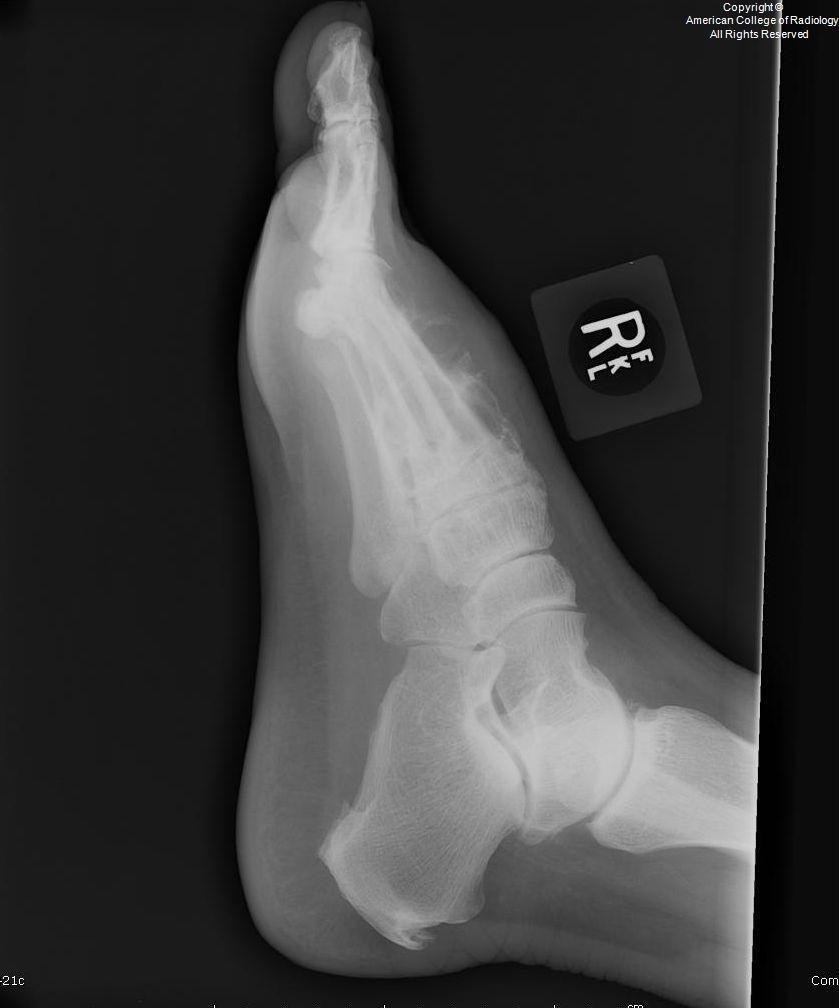

A

Medulla foot

• Medulla region in India

• also called mycetoma

• fungal (eumycetoma)

• bacterial (actinomycetoma)

• commonly seen in those who walk barefoot, such as agricultural workers

• patients typically present with painless swelling and a draining sinus tracts. The purulent discharge typically contains colored “grains” representing clumps of the causative organism

• Stage 0 – Soft-tissue swelling, which can become nodular and expansive.

Stage I – Extrinsic pressure on the bone causing bone displacement or scalloping. No bone involvement.

Stage II – Periosteal reaction or reactive sclerosis as a result of irritation of the bone surface by the causative organism.

Stage III – Bone erosion or cavitation as a result of penetration of the periosteum and cortex.

Stage IV – Joint involvement with longitudinal spread along a ray of metatarsal bone and phalanx.

Stage V – Horizontal spread limited to two rays of bone and confined to the hindfoot, midfoot, or forefoot.

Stage VI – Uncontrolled infection with multidirectional destruction